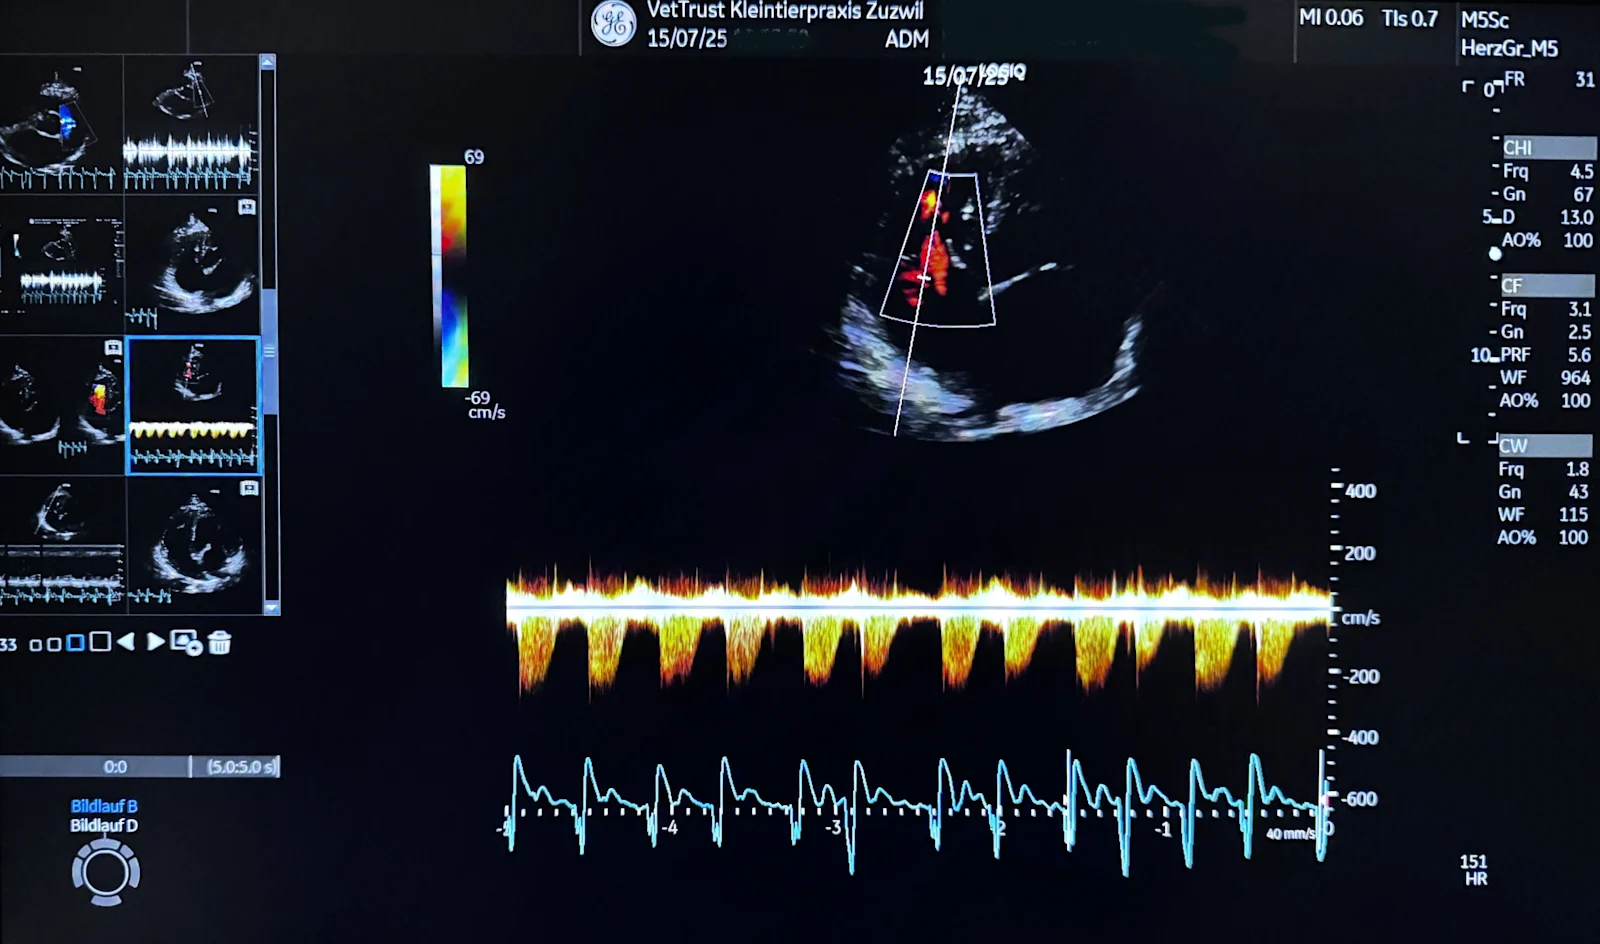

Modern cardiac ultrasound: precision through advanced equipment and leading expertise by Dr. med. vet. Tanja Rietmann (cand. CAS Cardiology Companion Animals ESAVS, Master of Small Animal Ultrasonography, Tech)

Standard systems may lack resolution or Doppler capabilities. The heart is complex and always moving. Tiny changes in valves, myocardium and blood flow require excellent image quality, processing power, suitable probes and modern, including AI-assisted, analytics.

At our specialized sites Zurich Ost, Basel and Zuzwil we perform echocardiography with multiple probes for patients from tiny puppies to giant breeds.